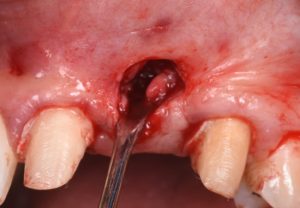

This video presents Part 2 of a staged pontic site development protocol, performed five months after the initial soft tissue augmentation. The objective of this second surgery is to further enhance soft tissue volume and achieve root coverage in preparation for a future fixed partial denture (FPD).

The procedure demonstrates the use of a horizontal vestibular incision with tunneling to mobilize the soft tissues and elevate the papillae. An autogenous connective tissue graft (CTG) harvested from the palate and maxillary tuberosity is utilized to augment tissue thickness. Additionally, a xenogenic bone graft is placed over the crestal area to serve as a space-maintaining scaffold and support vertical tissue stability.